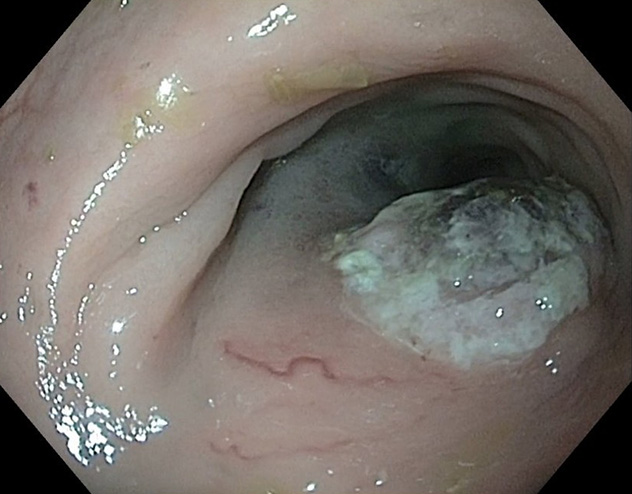

This image shows a large tissue resection in the stomach using a magnet traction device.

Our goal in this project is to develop techniques that allow for resection of large polyps and select early cancers through the endoscope that were previously not amenable to conventional endoscopic techniques. We're developing a new magnet traction device for use in a resection technique that is safe, efficient and easy to use.